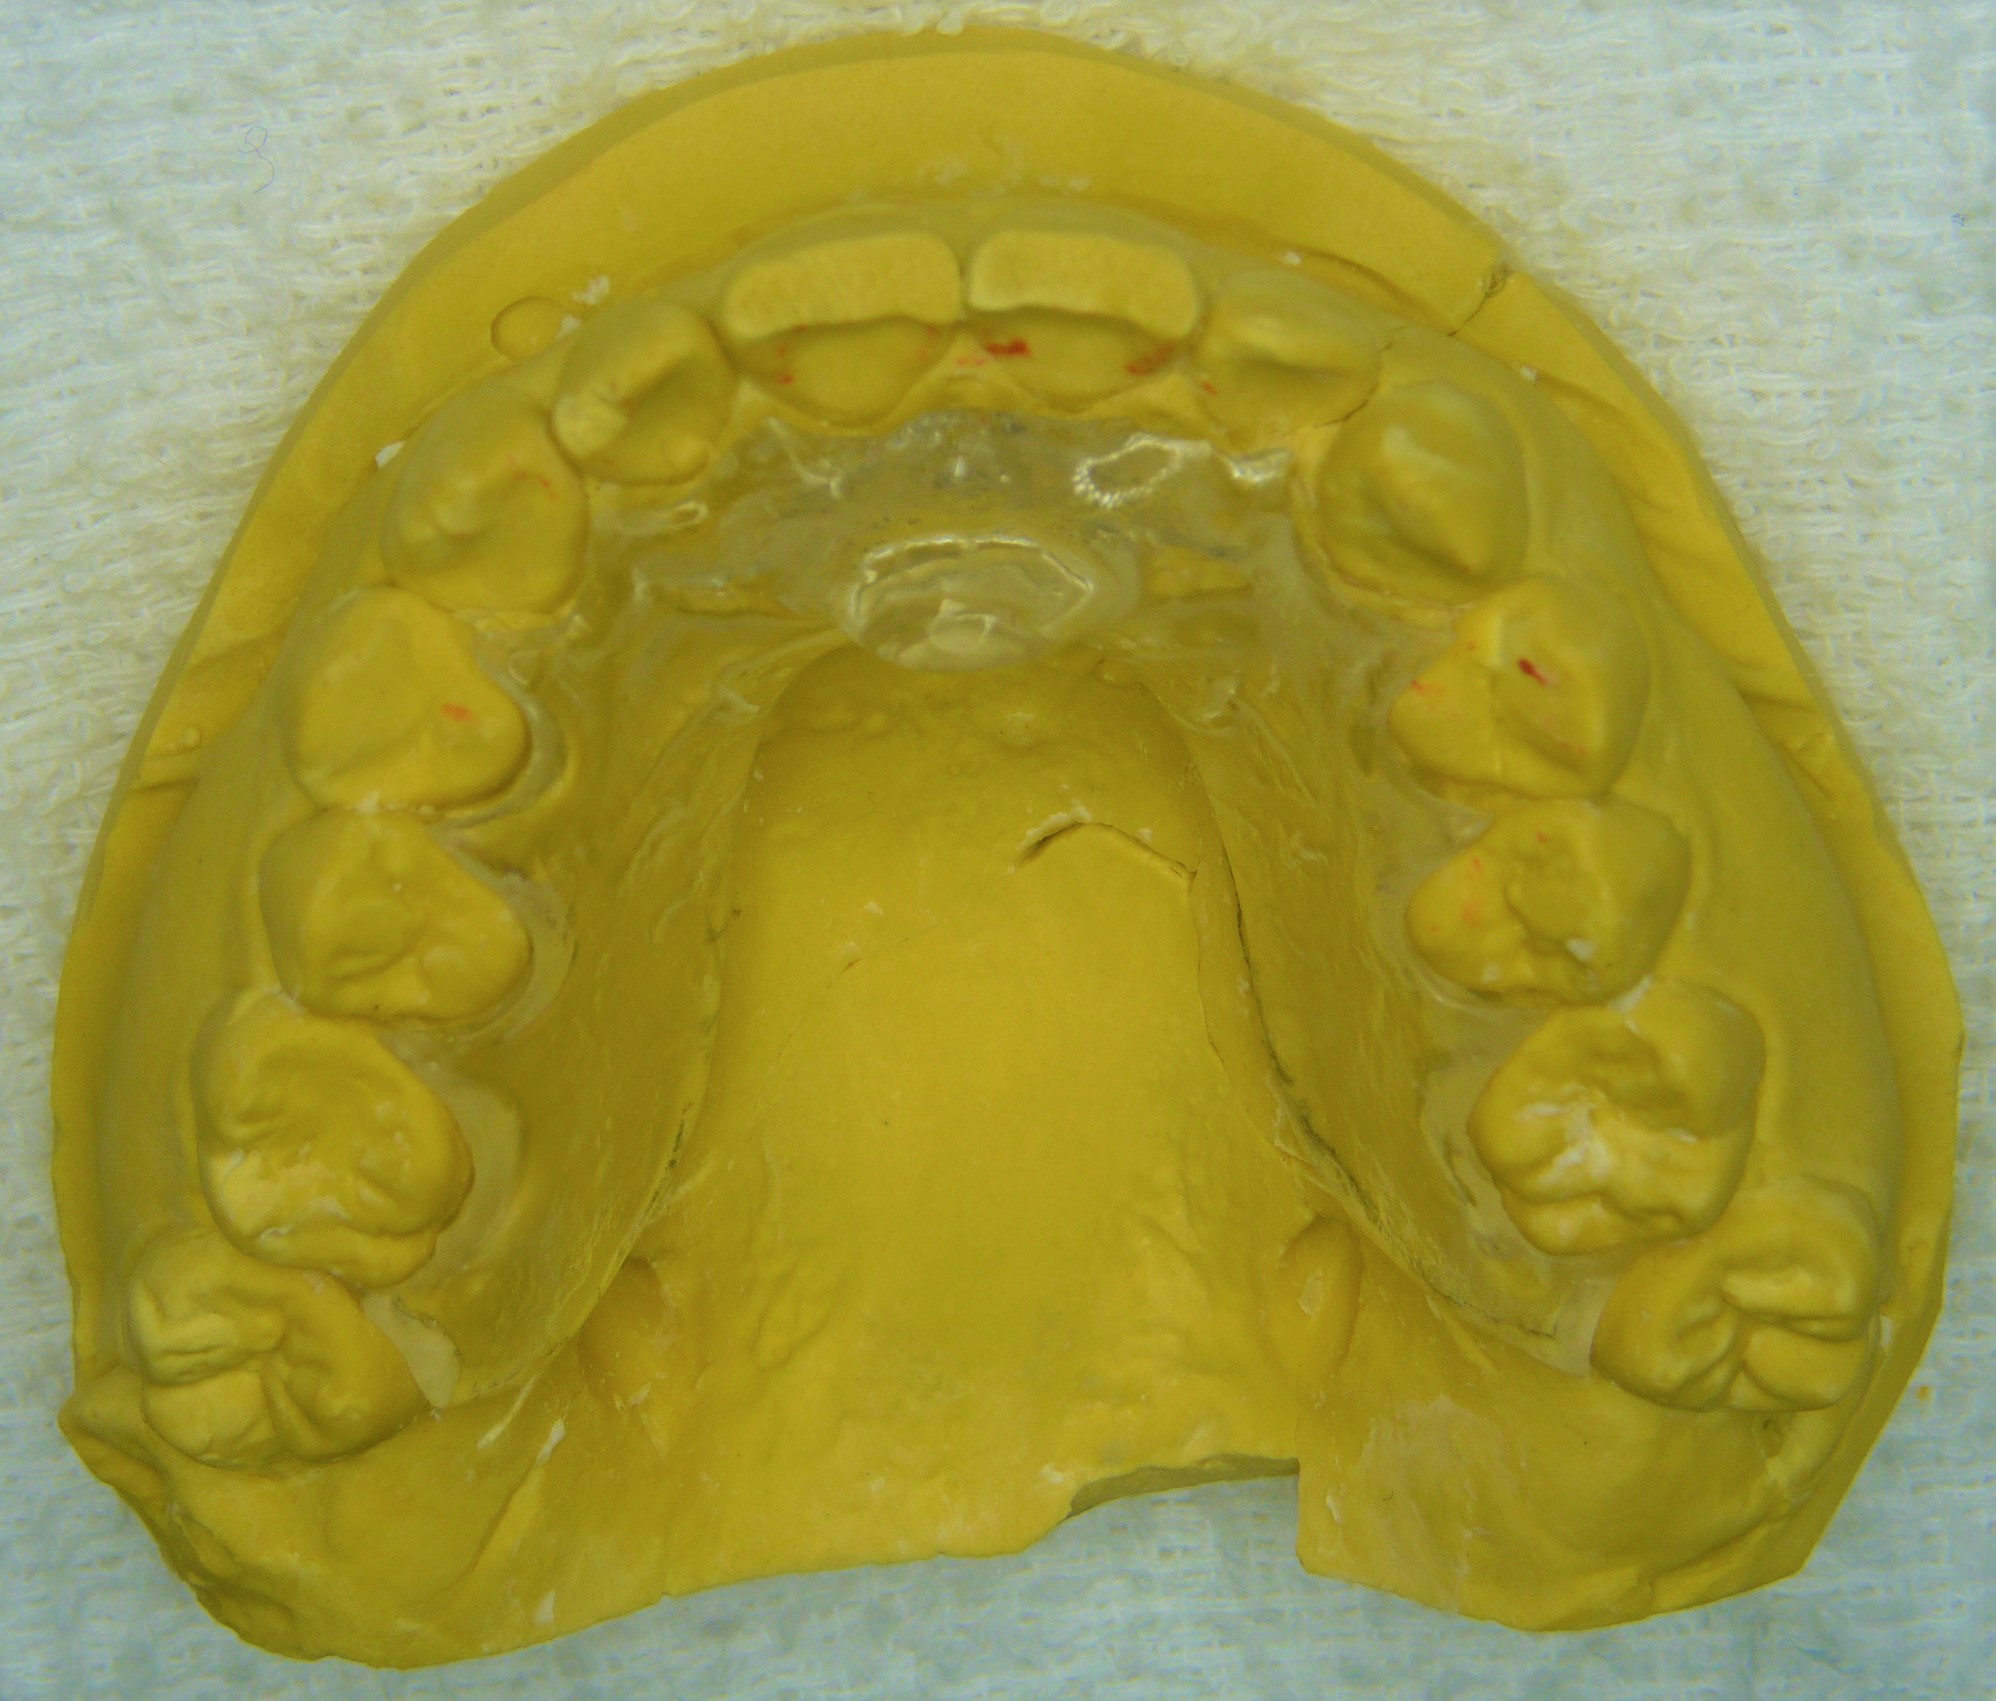

このたび義歯床用アクリリック樹脂(加熱重合レジン)を用いて義歯と同じく埋没法で作るように変更しました

外形などは全く変更ありませんので、ワックスアップしてから石膏で埋没します

割り出し以降は変わりません

技工作業をシンプルにするために色付けはせず透明です

作業模型を割らずに割り出した方が後の調整は楽です